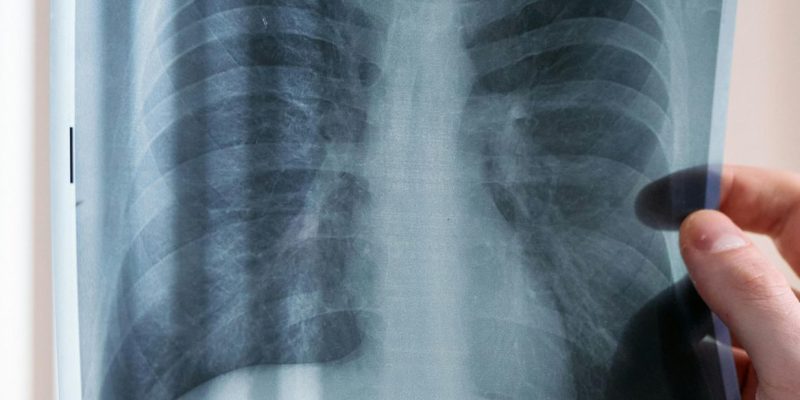

Pneumokokový zápal pľúc môže mať vážny priebeh – najmä u starších a chronicky chorých ľudí. Zápal pľúc je závažné ochorenie, ktoré môže viesť k hospitalizácii, zhoršeniu celkového zdravotného stavu, oslabeniu organizmu a – v niektorých prípadoch – aj k úmrtiu….

90-95 % všetkých infekcií dýchacích ciest je vyvolaných rôznymi respiračnými vírusmi, preto len malá časť z celkového počtu infekcií má byť liečená antibiotikami. Ako vieme odlíšiť vírusovú od bakteriálnej infekcie? Pacient si môže zakúpiť v lekárni samodiagnostický test, v ambulancii pomocou CRP analyzátora….